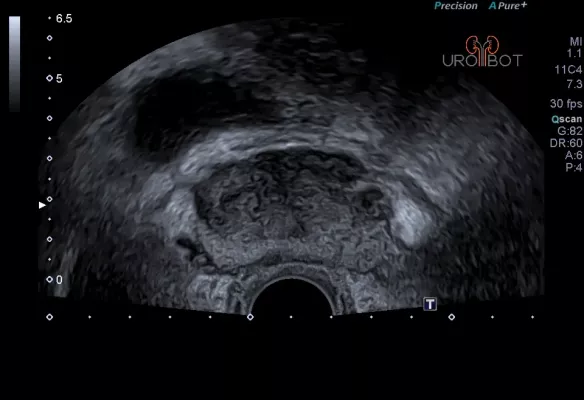

Transrektaler Ultraschall (TRUS)

Es handelt sich bei dieser Untersuchung um eine Ultraschalluntersuchung der Prostata. Dafür wird ein stabförmiger Ultraschallkopf in den Enddarm des Patienten eingeführt. Die Untersuchung kann in Seitenlage oder in Steinschnittlage durchgeführt werden. Mit der speziellen Ultraschallsonde kann die Prostata gleichzeitig längst und quer dargestellt werden. Beurteilt werden:

- Form,

- Größe,

- Abgrenzbarkeit,

- die verschiedenen Zonen der Prostata,

- Homogenität,

- Samenblasen.

Das Video zeigt eine sonographische Untersuchung der Prostata, durchgeführt über eine sogenannte transrektale Ultraschallsonde.